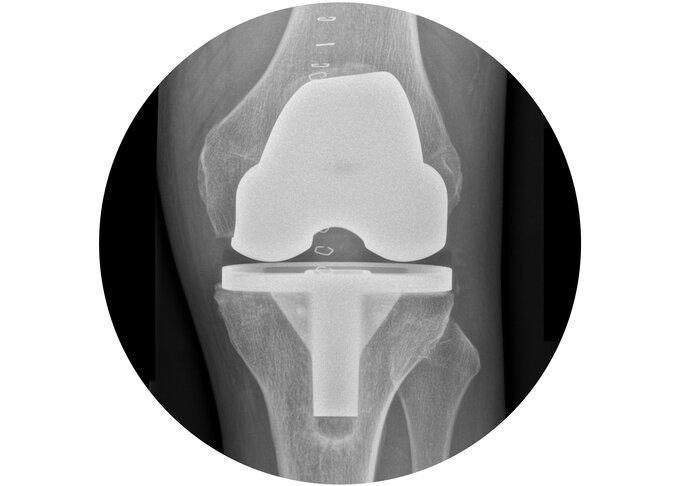

Endoprothetik

Eine Arthrose ist eine Verschleißerkrankung eines Gelenkes, bei der die gleitende Knorpelschicht verloren geht.

Bei einem fortgeschrittenen Knorpelschaden sind häufig Schmerzen, eine schlechte Beweglichkeit und ein Instabilitätsgefühl die Folge. Je nachdem, wie groß der Defekt des Gelenkknorpels ist, und ob die stabililisierenden Bänder mit betroffen sind, muss abgewogen werden, welcher Gelenkersatz der richtige ist.

Als Endoprothetikzentrum der Maximalversorgung erfüllt unsere Klinik die höchsten Ansprüche bei der Behandlung aller Formen der Gonarthrose sowie bei Prothesenlockerungen. Es steht jederzeit eine große Auswahl verschiedener Prothesenmodelle zur Verfügung um jedem Patienten die bestmögliche Versorgung zu gewährleisten.

Sollten von dem Knorpelverschleiß mehrere Gelenkanteile betroffen sein, so ergibt sich die Notwendigkeit eines vollständigen Oberflächenersatzes. Ist auch der Knorpel auf der Rückseite der Kniescheibe stark beschädigt und verursacht beschwerden, erfolgt außerdem der Ersatz der Kniescheibenrückfläche, der sogenannte Retropatellarersatz. Auch bei leichter Instabilität des Kniegelenkes kommt diese Prothese zum Einsatz, da sie die Möglichkeit hat, durch eine Variation das hintere Kreuzband zu ersetzen.

Bei ausgeprägten Fehlstellungen der Beinachse kann es häufig zu einer Instabilität der Bänder kommen, wodurch das Knie bei Bewegung keine stabile Führung mehr hat.

Im Falle der Lockerung einer bereits implantierten Prothese entstehen häufig größere Defekte am Knochen.

In beiden Fällen kann es notwendig sein, eine achsgeführte Prothese zu implantieren um das Gelenk zu stabilisieren. Bei dieser Kniegelenksprothese erfolgt die Kopplung mittels einer Scharnierverbindung beider Prothesenkomponenten des Ober- und Unterschenkels. Diese soll die Instabilität der Bänder ausgleichen und kompensieren. Größere knöcherne Defekte können durch zusätzliche Komponenten (sogenannte "Cones") aufgefüllt werden.

Eine achsgeführte Prothese ist in der Regel sofort nach der Operation voll belastbar. Wichtig ist anschließend eine intensive Beübung und Rehabilitation.

Abb. links: Röntgenbild einer gekoppelten Knie-Total-Endoprothese. Die obere Komponente sowie die untere sind in der Mitte durch einen Mechanismus miteinander stabil verbunden.

Abb. rechts: Gekoppelte Knie-Total-Endoprothese. Durch das Zwischenstück (Inlay) ist der Kopplungsmechanismus nicht zu sehen.